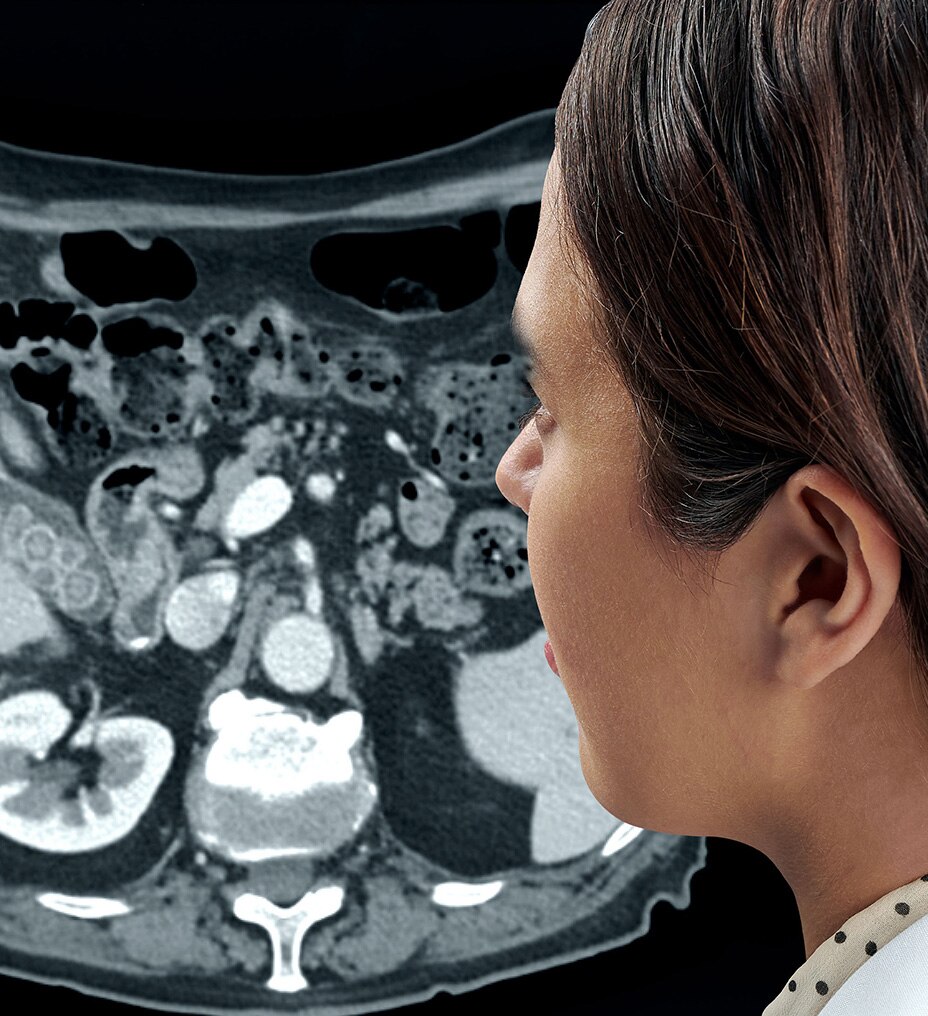

KLİNİK PERFORMANS

Klinik performansı yeniden tanımlıyoruz

BT deneyiminin en çok zaman alan kısmı taramanın kendisi değil; hastayı hazırlama, rekonstrüksiyon ve raporlama süresi gibi taramanın dışında kalan adımlardır. BT deneyimindeki tüm tarama öncesi ve tarama sonrası adımları analiz ettik ve önemli bulgularımızı Revolution Ascend'in tasarımına dahil ettik. Bu tasarımının sonucunda Revolution Ascend, yüksek BMI değerine sahip hastaları ve girişimsel prosedürleri verimli bir şekilde yönetebilme gibi yaygın endişeleri ortadan kaldırır. Ayrıca, tüm görüntüleme modları için kullanımı kolay iki düğmeli tarama sağlar.